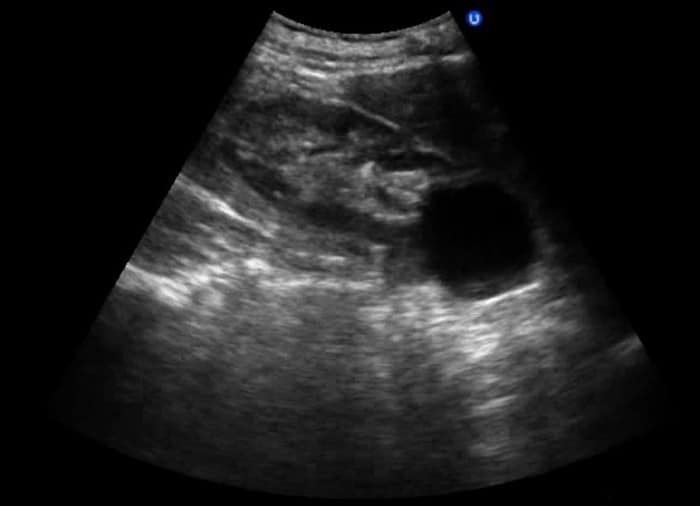

Прежде всего следует объяснить, что в почке анэхогенное образование не является заболеванием, а просто областью кистозного происхождения. Данное образование может впервые быть определено во время проведения ультразвукового исследования.

Анэхогенность в почке, как и в любом другом внутреннем органе в человеческом организме, свидетельствует о наличии любой жидкости, способной заполнить орган. На рентгеновском снимке такая аномалия представлена в качестве черного пятна.

Объемная аномалия в почке может присутствовать как в левой, так и в правой, а порой и в обеих. Анэхогенное образование имеет круглую или овальную формы, может занимать различное положение внутри почки и на поверхности. Киста бывает одна или несколько, имеющих отличающуюся структуру тканей и иметь на мониторе различные тени, перегородки, включения.

При ультразвуковом обследовании кисты выглядят как анэхогенные образования без кровеносных сосудов.

В нормальном состоянии почки здорового человека симметрично расположены, имеют четкую структуру и овальную форму. При их сканировании не отражаются ультразвуковые волны. Но при патологических изменениях или заболеваниях почек УЗИ может обнаружить гипер- или гипоэхогенные тела.

Гипоэхогенные образования (включения, тела) – это участок органа или полости имеющий сниженную акустическую плотность, по сравнению с окружающей его тканью. На мониторе они выглядят как черные пятна с четкими или размытыми краями имеющие акустическую тень или без таковой.